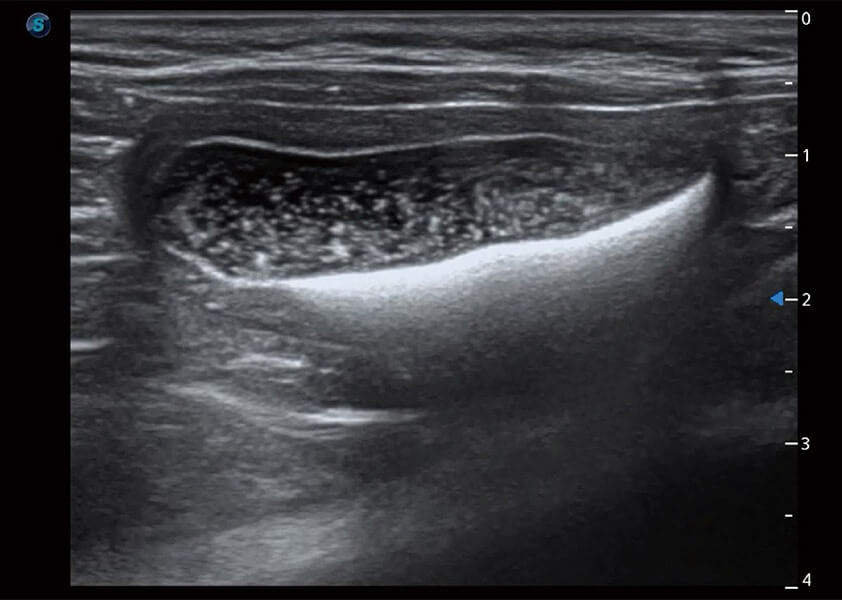

(犬)胆囊泥沙

ProPet 60 作为一款高端台式动物超声设备,为动物医生的日常诊断提供了一系列贴合动物临床需求、解决临床实际问题的高级成像功能。凭借全系列高清探头,满足医生对腹部、心脏、生殖、浅表、肌骨等成像的所有需求,切实帮助您提升检查效率,提高诊断信心。

专业的动物影像专用软件

ProPet 60专为动物医生设计,对不同的动物体型和生理结构作出了针对性的优化。通过动物影像专用软件,可满足个性化的应用需求,帮助动物医生获得更精确的诊断数据。